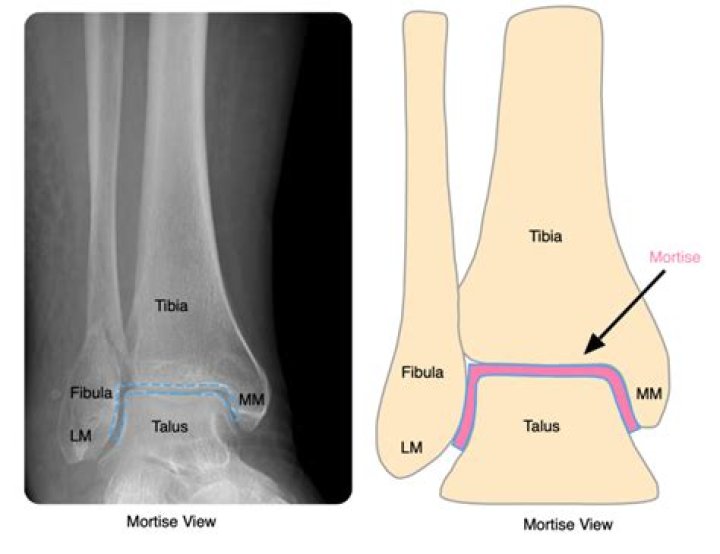

What is mortise in ankle?

The bony arch formed by the tibial plafond and the two malleoli is referred to as the ankle "mortise" (or talar mortise). The mortise is a rectangular socket.

How do you do a mortise view?

Patient position

1. the patient may be supine or sitting upright with the leg straightened on the table.

2. the leg must be rotated internally 15° to 20°, thus aligning the intermalleolar line parallel to the detector. ...

3. internal rotation must be from the hip; isolated rotation of the ankle will result in a non-diagnostic image.

Where is the mortise in the ankle?

The mortise view enables assessment for fractures and spacing of the entire joint surface, including that between the fibula and talus. The distance between the talus and either the fibula or tibia should be equal throughout the joint.

What is illustrated on a mortise view of the ankle?

The ankle AP mortise (mortice is equally correct) view is part of a three view series of the distal tibia, distal fibula, talus and proximal 5th metatarsal.